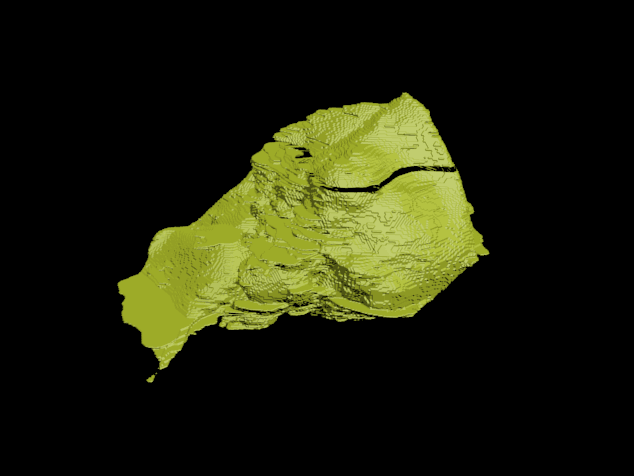

4, MarchingCube三维重建效果图

我的天,丑的吓人!但是这个丑讲道理是不能甩锅给MarchingCube的,要怪就怪图像识别做的不怎么样:)。(但在MarchingCube算法生成的模型还是比较多的明显锯齿)。

所以最后折衷一下做个网格简化吧!

好多了好多了!